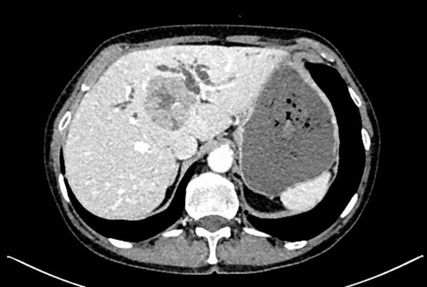

In der durchgeführten Staging-CT zeigte sich ein partielles Ansprechen (PR) mit Tumorgrößenreduktion von 49mm auf 33mm, die Lymphknoten blieben unverändert. Die Tumormarker sanken (AFP: 150, Ca19-9: 65). Aufgrund der persistierenden Diarrhö und des Verdachts auf einen Mischtumor erfolgte eine Umstellung der Therapie auf Cisplatin/Gemcitabin/Bevacizumab, wobei Gemcitabin ab Zyklus 2 wegen Fatigue auf 75% reduziert wurde und Cisplatin ab Zyklus 3 aufgrund von Ototoxizität abgesetzt werden musste. Nach vier Zyklen zeigte die MRT ein weiteres partielles Ansprechen (19×21mm), die Lymphknoten waren unverändert, die Tumormarker normalisierten sich erstmals.

Bildgebend können sich Mischtumoren wie ein HCC-iCCA-Gemisch imponierend darstellen, wie ein typisches HCC oder aber ein typisches iCCA aussehen oder sich unspezifisch darstellen. Bildgebende Hinweise auf Mischtumoren bestehen bei verschiedenartigem Kontrastmittelverhalten innerhalb eines Tumors (im Verlauf zunehmende Anreicherung, Anreicherung mit Wash-out, Anreicherung ohne Wash-out oder Hypovaskularisierung), vaskulärer Invasion und Gallengangsbeziehungen. Die Kombination erhöhter Tumormarker (AFP und Ca19-9) kann einen Hinweis liefern, ist aber nicht beweisend.